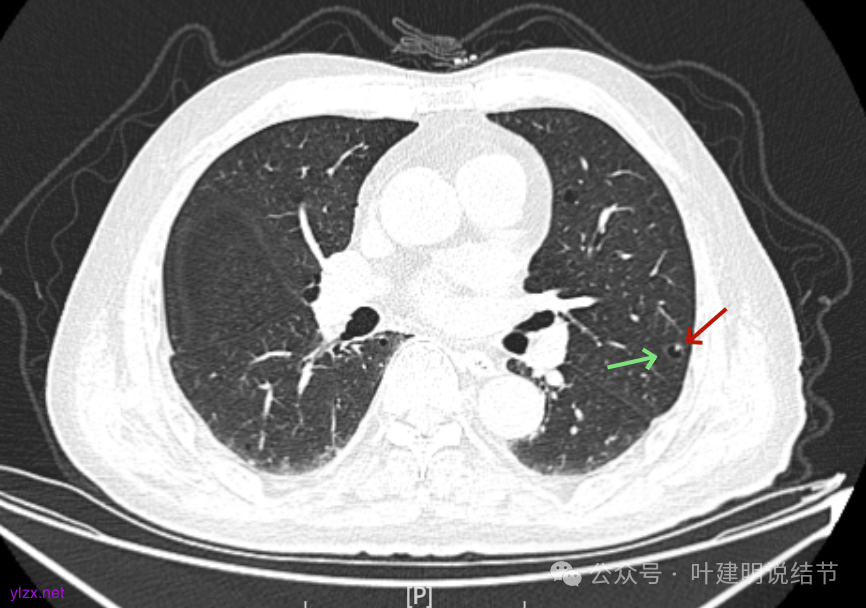

先来看2025年1月的影像:

病灶囊壁稍不均,多密度较高,表面欠平。

病灶整体的囊壁稍不均,靠内侧有磨玻璃成分。

囊壁不厚但密度较高。

囊腔内壁稍显不光滑,有少许突起于囊腔内。

上图也见囊腔内壁有突起,此层囊壁大部分呈磨玻璃密度。

边缘区是淡磨,内壁少许突起。

左肺上叶红色这处是囊腔型病灶,囊壁略不均,似有微小血管进入囊壁,对比2023年4月整个囊腔来讲有扩大,需要考虑囊腔型肺癌的可能性大。右侧蓝色的并不是典型囊腔型肺癌的表现,再加上两肺绿色这些慢支肺气肿与肺大泡的影像,右侧的就更加不确切,至少近期不能够考虑右侧也要开刀的事情。其实左侧的主病灶相对于其他表现更典型的囊腔型肺癌来说,由于囊壁密度偏高,也不是百分百必定是肺癌。我的想法还是先等脑梗情况稳定,并且间隔4~6个月复查病灶再有进展在考虑单孔胸腔镜下局部切除就可以。淋巴结可以考虑采样,但一般不至于阳性。破是不会切破的。消融不建议,囊腔灶更难通过穿刺获得病理依据,况且东西在边上,能局部楔切,当然首选手术。意见供参考!

左侧这个病灶总体上看仍是囊腔型肺癌可能性大些,但因为其两肺存在多发肺大泡的基础,而且囊壁除了结节状高密度的以外,其他的部分虽欠均匀,但差别并不太大。所以100%恶性还是难以认定的。假如没有脑梗情况,位置在边上,早点切了明确并去除病灶当然是可行的。但在反复脑梗发作的情况下,本身要神经内科情况稳定再手术较为安全,加上无法确切认定必恶性,再适当的随访也不至于影响预后。所以仍是利弊权衡与如何平衡的事情。对于这种囊腔灶,或囊肿为表现的肺癌,其实穿刺不容易阳性,针越过组织的距离并不长,其内又是空的或是液体性质的。从临床经验来看,囊腔型肺癌若囊壁是实性的,确实低分化类型的更常见些,相对风险较高些。但若是囊壁磨玻璃成分的,则也仍是贴壁为主型多见。而且从大小来讲,个人总觉得囊腔部分不能算大小,肿瘤的有形成分应该是减去空腔部分的,所以不能认定CT上测量的包括囊腔部分的来算肿瘤大小的T值。